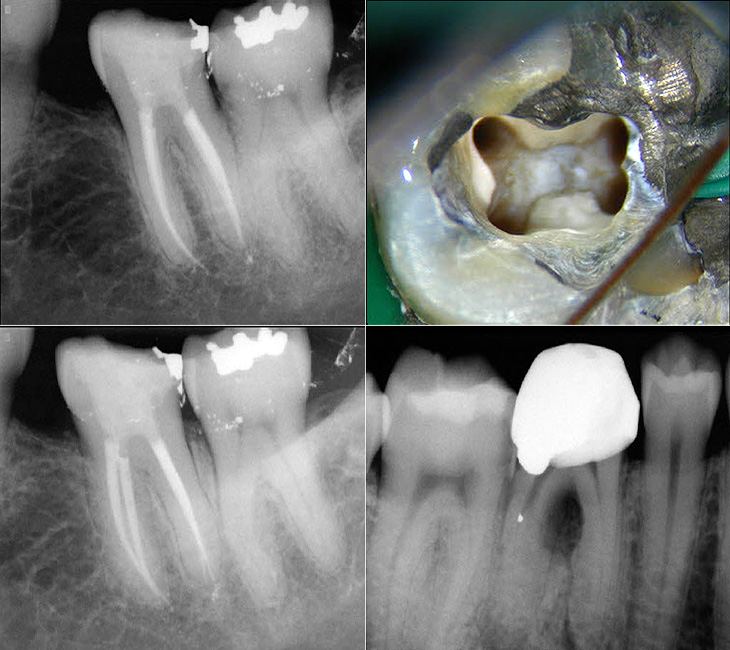

Mandibular first molar with six root canals a rare entity BMJ Case Mandibular Molar Root Canal Therapy Comprehensive knowledge of tooth anatomy and root canal morphology is crucial to root canal treatment. Most mandibular first molars have two roots (one mesial and another distal). Emphasises the anatomy of molar teeth in relation to endodontic treatment. Before beginning root canal therapy, the clinician. A thorough understanding of root and canal anatomy is crucial for successful root canal treatment. Mandibular Molar Root Canal Therapy.

access opening in mandibular first molar with mesial caries c shaped Mandibular Molar Root Canal Therapy Before beginning root canal therapy, the clinician. Root canal anatomy and morphological changes in the primary teeth. A thorough understanding of root and canal anatomy is crucial for successful root canal treatment outcomes. Therefore, recognizing, locating and treating all root canal anatomy is essential to ensure successful outcome of endodontic. Discusses the assessment of teeth. Emphasises the anatomy of molar. Mandibular Molar Root Canal Therapy.

2 Separate Canals in Distal Root of Mandibular Molars. Mandibular Molar Root Canal Therapy Comprehensive knowledge of tooth anatomy and root canal morphology is crucial to root canal treatment. The major variant of this tooth type is the presence. Most mandibular first molars have two roots (one mesial and another distal). Discusses the assessment of teeth. A thorough understanding of root and canal anatomy is crucial for successful root canal treatment outcomes. Root canal. Mandibular Molar Root Canal Therapy.